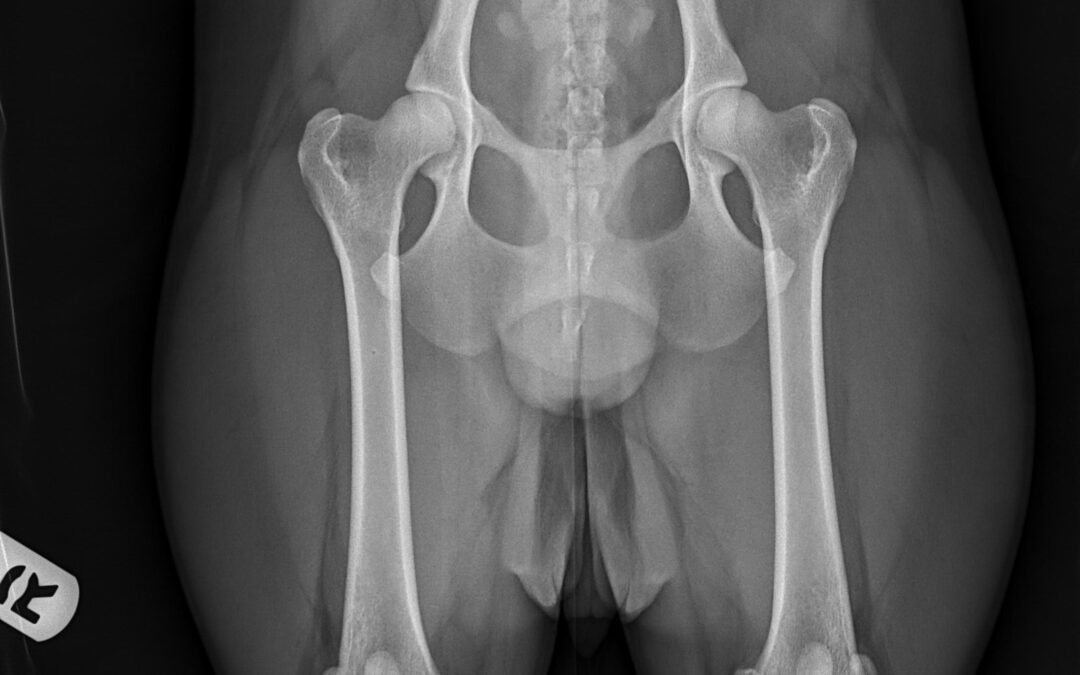

Have you ever heard about Dog Hip Dysplasia? Dog hip dysplasia is a genetic condition that affects the hip joint, where the ball and socket of the hip do not fit together properly. In dogs with hip dysplasia, the joint is loose and unstable, causing the ball to move...